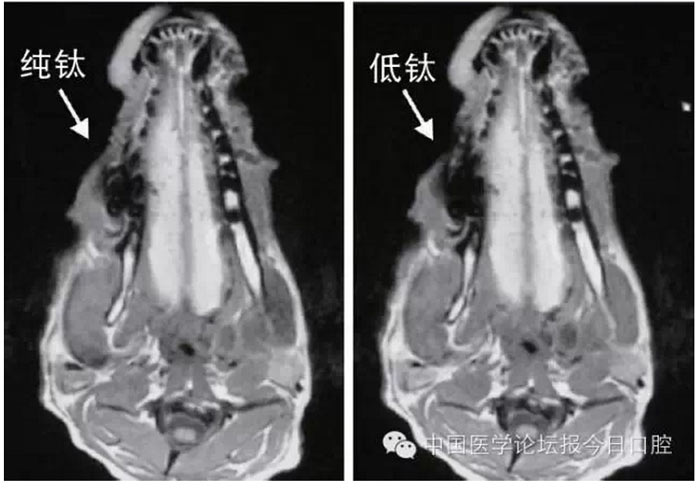

文獻(xiàn)研究中常使用的金屬包括鎳鉻合金、鈷鉻合金、低鈦合金、純鈦、金合金、金鈀合金、銀鈀合金等成分如表所示。大量研究得出近乎一致性的結(jié)論。金合金、金鈀合金、銀鈀合金對(duì)MRI影響甚微,與全瓷材料、丙烯酸樹(shù)脂極為相似,表現(xiàn)為修復(fù)體影像邊緣光滑、無(wú)變形、無(wú)偽影;純鈦金屬對(duì)MRI影響較小,接近于全瓷材料;但有的研究卻發(fā)現(xiàn)純鈦在核磁共振場(chǎng)中也產(chǎn)生偽影,但偽影涉及的掃描層數(shù)較少;低鈦合金(鈦合金)對(duì)MRI影響較大,介于純鈦和鎳鉻合金之間,中度偽影;鎳鉻合金、鈷鉻合金對(duì)MRI影響很大,鈷鉻合金更甚;表現(xiàn)為重度偽影、圖像扭曲變形(圖1、圖2)。不難看出,對(duì)MRI 影響,全瓷材料、樹(shù)脂材料<金合金等貴金屬<純鈦<低鈦合金<鎳鉻合金<鈷鉻合金。有研究發(fā)現(xiàn)鈷鉻合金橋偽影大小與修復(fù)體長(zhǎng)軸一致,影響范圍為固定橋近遠(yuǎn)中徑2倍,頰舌徑的4倍;相同外形金屬修復(fù)體厚度增加,偽影增加。單個(gè)金屬樁核偽影可波及到上頜竇、牙槽骨、舌體、舌下腺等組織器官,但對(duì)眼底、眼內(nèi)容物、腦組織和頸椎成像基本無(wú)影響。

圖2 4種金屬冠在犬MRI檢查中的影響,圖片引自《實(shí)用口腔醫(yī)學(xué)雜志》2014第30期《4種金屬冠對(duì)磁共振成像影響的對(duì)比研究》一文,作者高嵐等